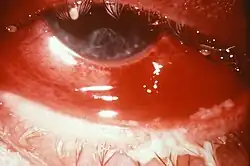

Eine Gonokokkeninfektion der Augen (Okulare Gonorrhoe, „Augentripper“) wird bei Erwachsenen zumeist durch Selbstinokulation, also durch Reiben der Augen nach dem Berühren infizierter Genitalien verursacht. Die Infektion kann schwerwiegend verlaufen, aber auch milde und asymptomatische Verläufe sind möglich. Symptome sind stark geschwollene Augenlider, starke Hyperämie (erhöhte Durchblutung) und starke Eiterbildung. Lytische Enzyme von infiltrierenden Granulozyten der Immunantwort können gelegentlich Geschwürbildung an der Cornea verursachen, in ernsten Fällen sogar Perforationen. Hier sind eine schnellstmögliche Diagnose und Behandlung erforderlich.

Gonokokkeninfektionen während der Schwangerschaft können ernsthafte Komplikationen zur Folge haben. Im ersten Trimester können Entzündungen von Bauchfell und Eileiter den Verlust des Fötus zur Folge haben, im zweiten und dritten Trimester sind aufsteigende Infektionen eher selten, da ein Schleimpfropf die Gebärmutter verschließt. Die häufigste Art der Erkrankung von Neugeborenen nach einer Ansteckung durch die Mutter ist die Gonoblennorrhoe (auch Ophthalmia neonatorum), eine Infektion der Augen, resultierend aus dem Kontakt mit Krankheitserregern in den Sekreten der Gebärmutter. Blindheit kann die Folge sein. Um dies zu vermeiden, wird direkt nach der Geburt eine Credé-Prophylaxe („Augentripperprophylaxe“[9]) durchgeführt, bei der Augentropfen verabreicht werden, die eine antibakterielle Wirkung haben. Andere, seltenere Manifestationen bei Neugeborenen sind Entzündungen der Schleimhäute in Nase, Vagina und After, und sind häufig asymptomatisch.